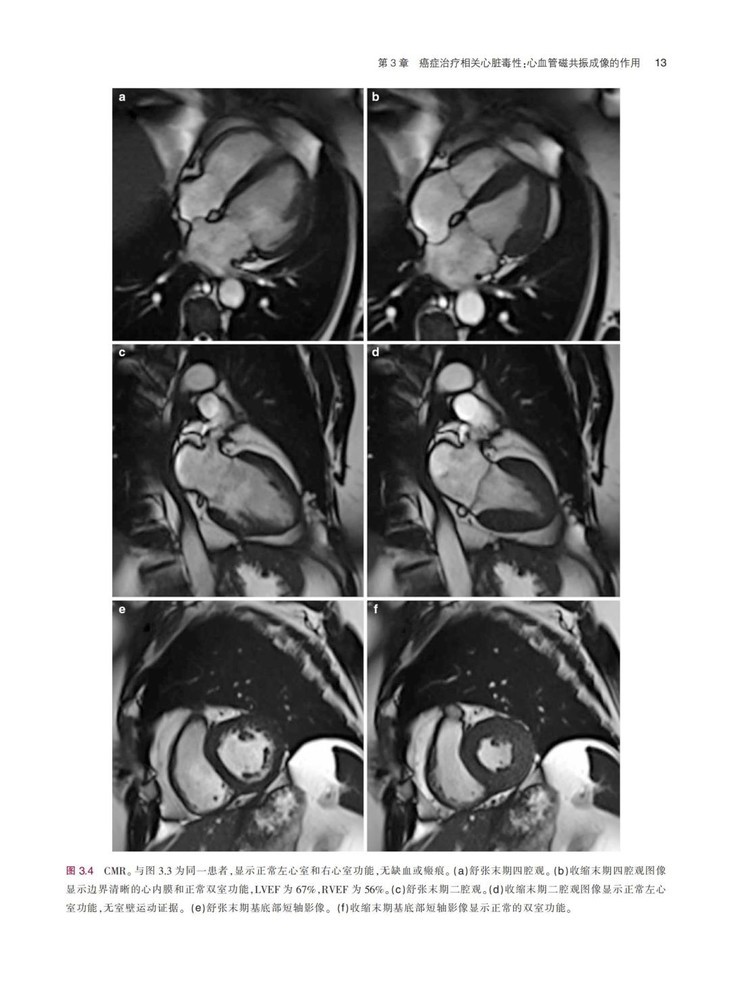

《临床肿瘤心脏病学图解指南》一书结合丰富的临床病例,系统地描述了癌症与心血管领域常见的临床问题,患者主要为既往有心血管疾病的癌症患者,或癌症患者继发复杂心血管疾病,全书对疾病的诊断、检查方式、治疗方式等内容进行了详细阐述,并配有大量的图片,可帮助读者更加清晰地了解相关内容。本书通过结合相关临床病例的方式,在强化理论的同时,突出临床应用特性。本书对我国临床肿瘤心脏病学的基础研究和临床实践有明确的指导意义,对于肿瘤或心血管领域的临床医师及相关研究者具有很强的参考价值。

配有大量手术图片和超声图片,图文并茂,可以为读者提供临床指导,实用性很强